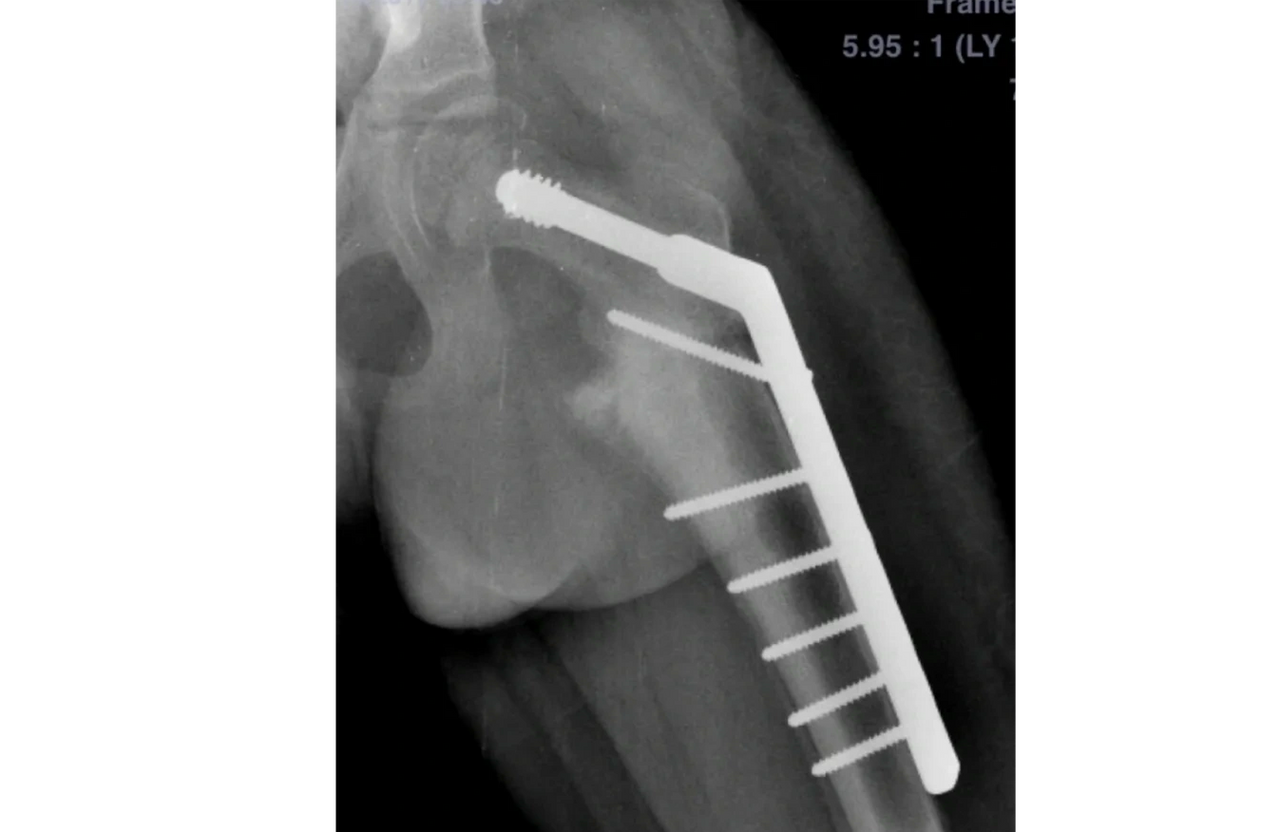

The bone was straightened out and fixed with a specialised plate and screws and went on to unite.